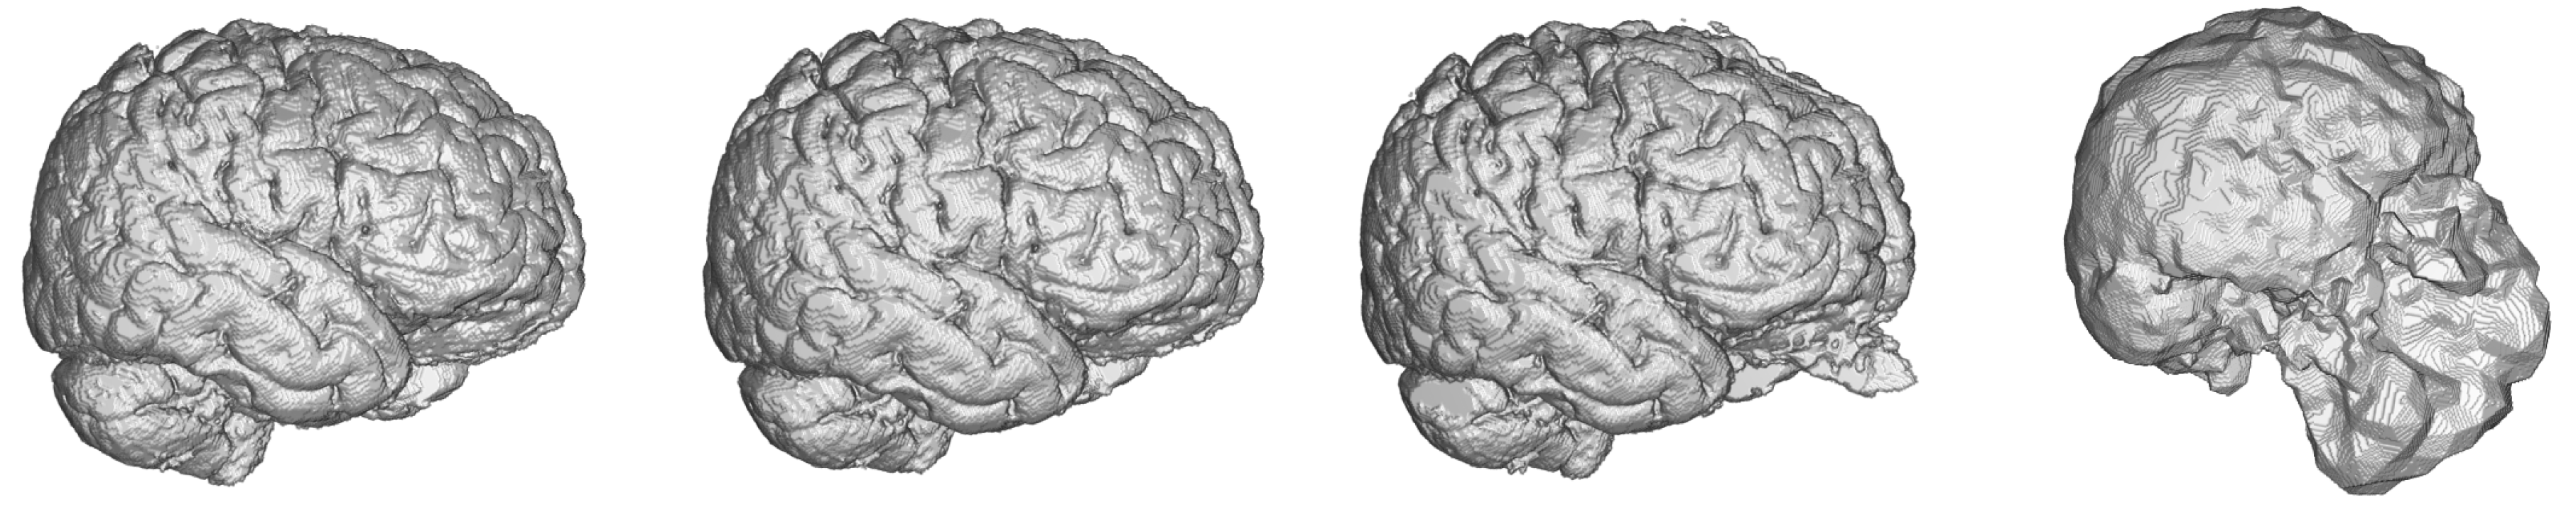

Dense-U-Net network proved to give the best performance in all considered metrics in 3D processing mode. There should be stated, that even segmentation using basic U-Net network gave better accuracy than a human expert. When compared to other 2D networks, the Dense-U-Net had better results in all metrics except for average Hausdorff distance. This is most probably caused by the fact that 50 epochs of training was not enough for a network with so many parameters and therefore the network generated more artifacts in the output segmentation than the simpler versions. As can be seen in Figure 7 the methods had problems segmenting the area around nasal cartilage. FSL method results in this case were unusable for medical praxis. Dense-U-Net network had the best results also thanks to the fact, that it was able to successfully segment this area on the MRI scan.

Figure 7.

Visualisation of predictions from 3D benchmark brain models and FSL segmentation. From left to right—Dense-U-Net, Residual-U-Net, U-Net, FSL.

The Dense-U-Net network was trained in the fine-tuning phase (99 epochs) and validated using 3-folds cross-validation. In all five metrics the results are more accurate than a human expert. Output of the segmentation is visualised in Figure 8. It is clearly visible, that the proposed segmentation output overcame the human results and also results of older methods not based on deep neural networks such as the FSL. The network was able to learn the input image features as well as to generalize the brain segmentation problem. All the evaluations were made using data independent to training and the validation data.

Figure 8.

Comparison of ground truth brain model (left) and brain model segmented by Dense-U-Net (right) after the final phase of training.